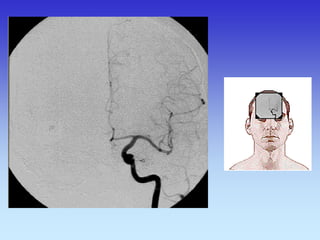

METODE PRIKAZA KRVNIH ŽILA

•UZ-DOPPLER

•DSA

•CTA

•MRA

VASKULARNA OPSKRBA WILLIS-ijev prsten

a. cerebri ant.

a. cerebri media

a. cerebri post.